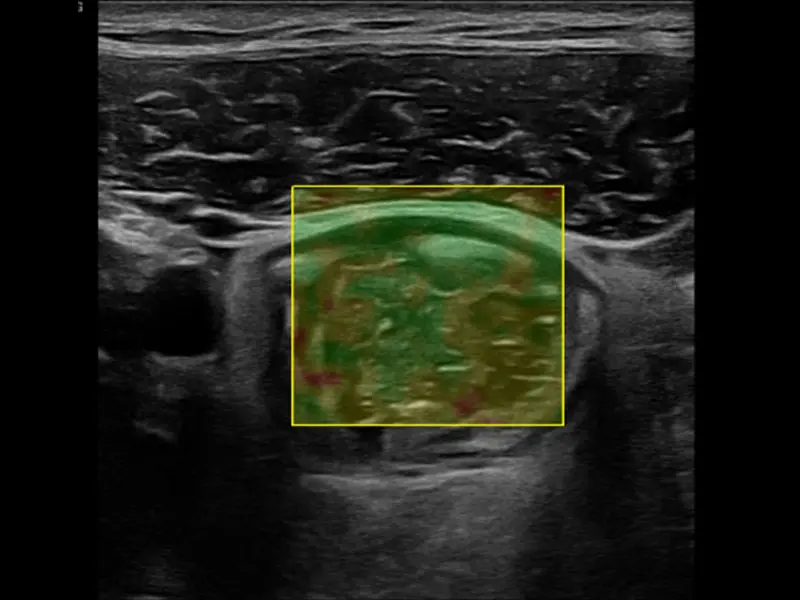

Powering the procedure is a high-definition machine from Samsung (the RS85 Prestige) that is more advanced than traditional ultrasound, permitting shear wave elastography with high-quality images that can highlight any scar tissue or chronic damage to the bowel. “It’s especially helpful when you can show patients in real time their disease activity, improvement, or remission,” says Dr. Dolinger. “And it can be convincing for parents who are faced with the decision of starting a child on lifelong immune therapy.”

A shear wave elastography—how we measure scar tissue in the small intestine.